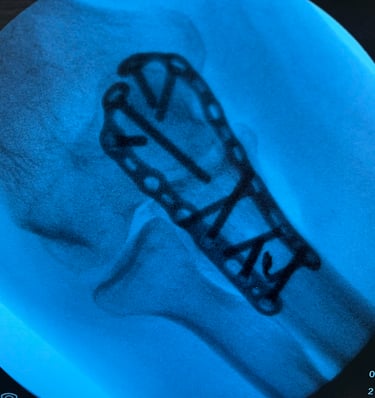

Mi occupo del trattamento delle principali patologie del gomito, tra cui tendiniti (come epicondilite ed epitrocleite) e traumatologia del gomito. Eseguo inoltre il trattamento chirurgico delle rotture del tendine distale del bicipite, con tecniche finalizzate al recupero della forza e della funzionalità dell’arto superiore.